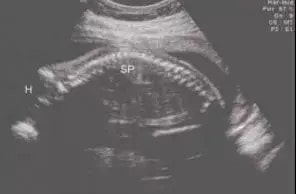

宝宝在妈妈的肚子里时候一直是蜷缩状,整个脊柱是一条向后弯的 C 型。

妇科与产科超声图谱

宝宝出生后,脊柱还是 C 型的,平躺时脊椎和颈椎就是一个平面,这时非要硬塞一个枕头进去,不但不舒服,还会阻隔宝宝顺畅的呼吸。